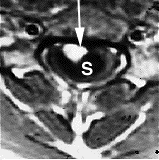

| MRI image shows spinal bleeding (myelomalacia). |

There are two tests that can provide a definite diagnosis of myelomalacia; magnetic resonance imaging (MRI), or myelography.[8] Diffuse hyperintensity on T2-weighted imaging, and hypointensity on T1-weighted imaging of the spinal cord can be an indication of the onset or progression of myelomalacia